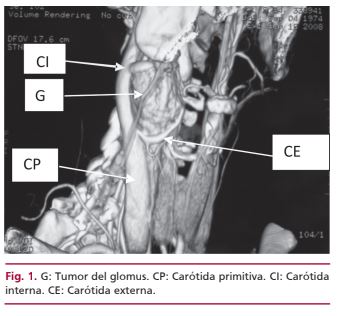

Los tumores del glomus carotídeo se caracterizan por su vascularización importante y su manejo preoperatorio puede incluir la embolización percutánea previa a la resección quirúrgica. Esta técnica disminuye la hemorragia y el tamaño del tumor y hace menos riesgosa la disección, con reducción de la morbimortalidad. Una técnica alternativa es la interrupción de la irrigación del tumor mediante la colocación de un stent cubierto en la carótida externa, que es la vía principal de irrigación. Esta técnica es útil en especial en tumores grandes y evita el riesgo de embolia intracraneal cuando se emplean coils para realizar la embolización. En esta presentación se describe el caso de una paciente de 31 años tratada de esta manera; se le colocó el stent y 24 horas después se realizó la resección del tumor.